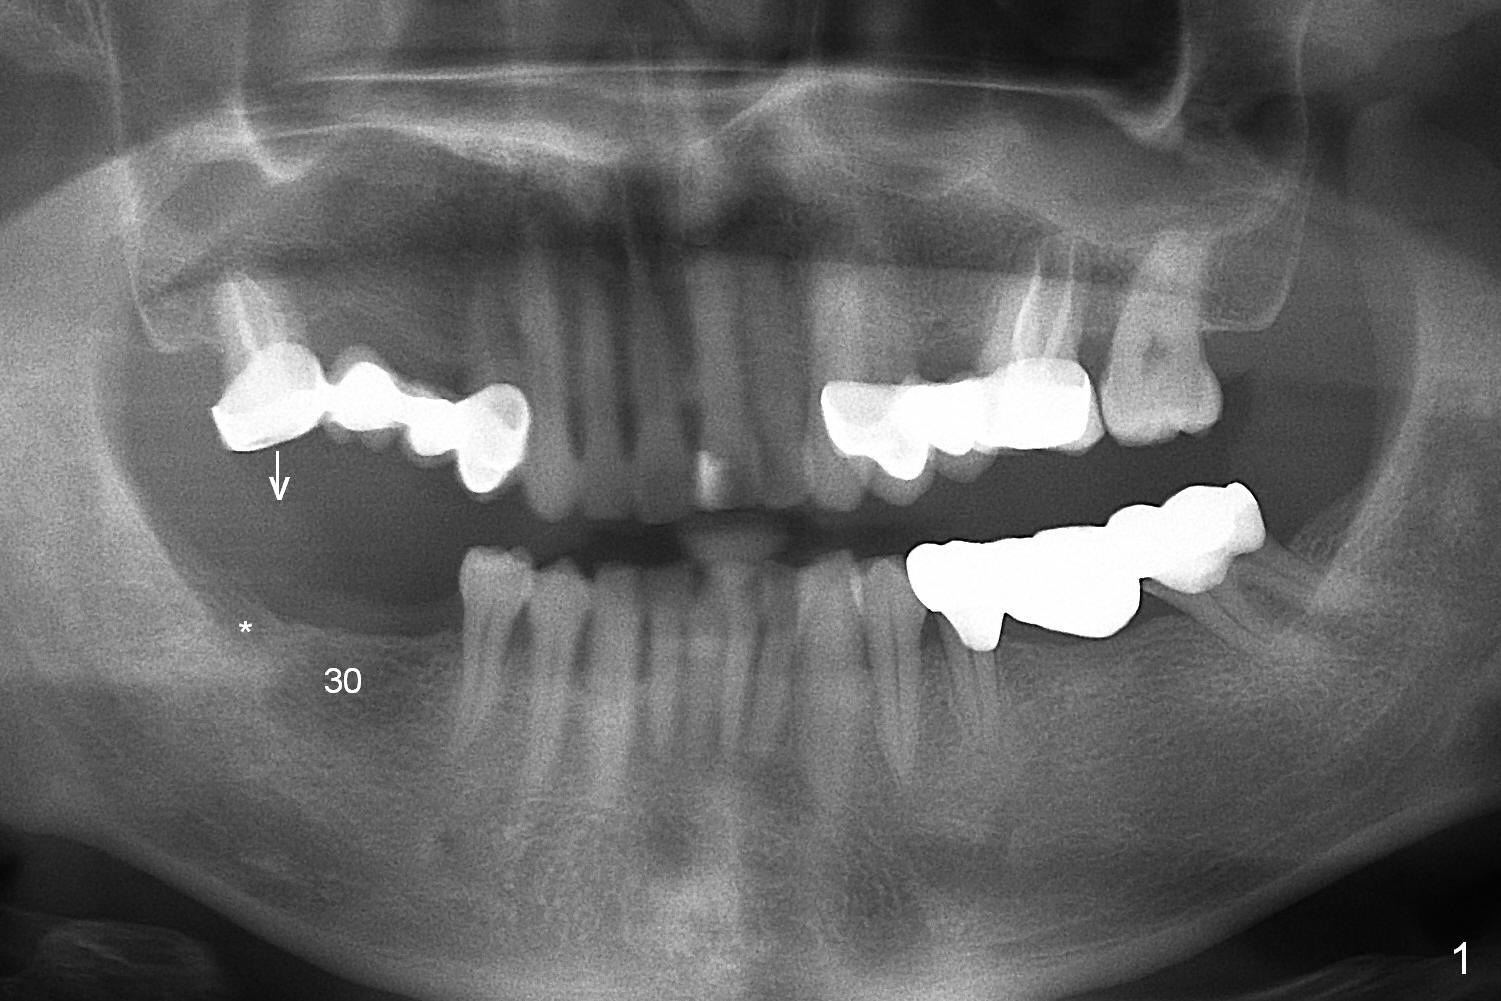

A surgical stent for the lower right quadrant is to be placed as a guide to reduce #2 occlusion (Fig.3 *). Wax up shows that the pontics at #3 and 4 are infraocclusal. It appears that the upper right bridge should be removed. Implants are placed at #3 and 4 and new crowns are fabricated at #2 and 5 to have normal occlusion.

Ridge atrophy at #30 and 31 is mild to moderate (Fig.4).